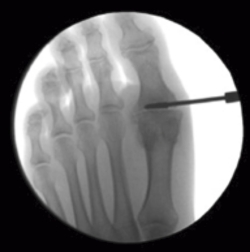

Durante toda la cirugía es necesaria la utilización del aparato de rayos X de tipo Fluoroscan® (Figura 5).

Figura 5. Imagen del Fluoroscan® al acabar la intervención. Puede observarse la correcta alineación y coaptación ósea y, también, restos de papilla ósea alrededor de la articulación.